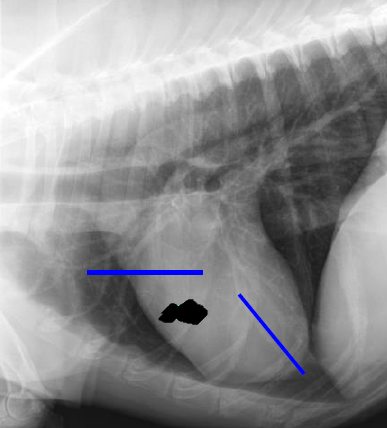

Lateral

5 to 9

Right ventricle

12 to 2

Left atrium